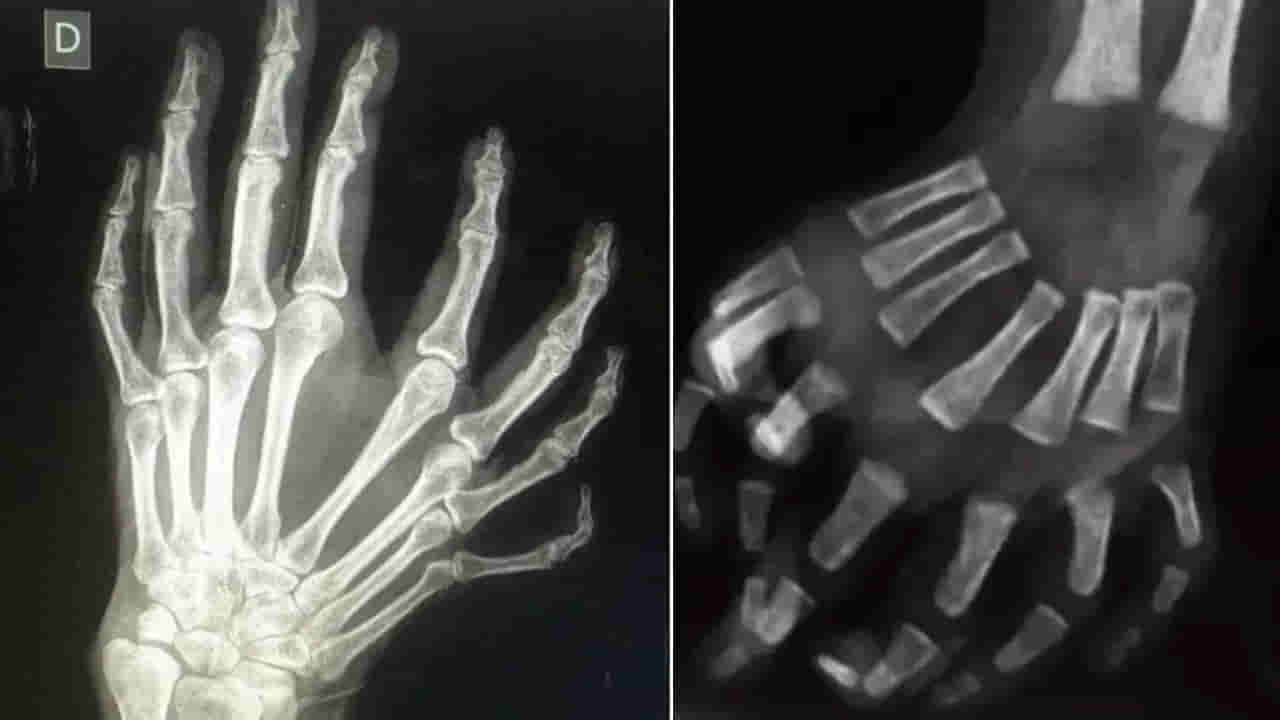

మిర్రర్ హ్యాండ్.. ఈ అరుదైన వ్యాధితో ప్రపంచంలో చాలామంది బాధపడుతున్నట్లు డాక్టర్లు చెబుతున్నారు. ఈ అరుదైన మిర్రర్ హ్యాండ్ సిండ్రోమ్ను ఉల్నార్ డైమెలియా(Ulnar Dimelia) అని కూడా అంటారు. ఈ సిండ్రోమ్తో బాధపడుతున్న వ్యక్తులకు సాధారణంగా ఏడు లేదా ఎనిమిది వేళ్లు ఉంటాయి. వీరికి బొటన వేలు ఉండదు. ఈ వ్యాధి దేని వల్ల వస్తుందోనన్న కారణాలు ఏవిలేవు గానీ.. ఇది పుట్టినప్పుడు లేదా ప్రసవానికి ముందు అల్ట్రాసౌండ్లో నిర్ధారిస్తారు.

ఎవరైనా కూడా ఈ మిర్రర్ హ్యాండ్ సిండ్రోమ్తో జన్మించినట్లయితే, ఆపరేషన్ ద్వారా దీనికి చికిత్స చేయవచ్చు. అయితే ఈ శస్త్రచికిత్సతో చేతి పనితీరు లేదా దానికి రూపం మారుతుంది. 2018లో యూఎస్ నేషనల్ లైబ్రరీ ఆఫ్ మెడిసిన్లో నివేదించిన ఓ కేసు ప్రకారం.. పాలీడాక్టిలీ(Polydactyly) అనే వ్యాధి వల్ల రెండు నెలల బాలిక అదనపు వేళ్లు కలిగి ఉంది. ఆ చిన్నారికి అనేక శస్త్రచికిత్సలు జరిగిన తర్వాతే.. ఆమె చేతికి సాధారణ సంఖ్యలో వేళ్లు ఉన్నాయి.

ఇదిలా ఉంటే.. ఈ నివేదిక ప్రచురించే సమయానికి ఉల్నార్ డిమెలియాతో 70 కేసులు మాత్రమే నమోదయ్యాయి. ‘ఎగువ అవయవాల సరైన రీతిలో అభివృద్ధి చెందకపోవడం వల్ల ఏర్పడేది ఈ మిర్రర్ హ్యాండ్ సిండ్రోమ్’ అని డాక్టర్లు వెల్లడించారు. ‘టైప్ 2 ఉల్నార్ డైమెలియా విషయంలో శస్త్రచికిత్స ద్వారా చేతి శరీర నిర్మాణాన్ని సరి చేసుకోవచ్చు. అయితే ఇది పూర్తిగా బాధితుడి అంగీకారంతో జరుగుతుందని వైద్యులు చెప్పారు.(Source)